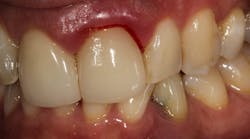

This patient presented with discomfort and mobile teeth Nos. 24 and 25. Extractions were performed, and the area was allowed to heal for six months. Mini-implants were placed in site Nos. 24 and 25 and immediately loaded with temporary crowns. The final splinted restoration was cemented two weeks later.

Figure 9: Implants restored two weeks after placement